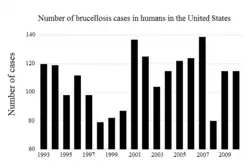

United States

Dairy herds in the U.S. are tested at least once a year to be certified brucellosis-free[58] with the Brucella milk ring test.[59] Cows confirmed to be infected are often killed. In the United States, veterinarians are required to vaccinate all young stock, to further reduce the chance of zoonotic transmission. This vaccination is usually referred to as a "calfhood" vaccination. Most cattle receive a tattoo in one of their ears, serving as proof of their vaccination status. This tattoo also includes the last digit of the year they were born.[60]

The first state–federal cooperative efforts towards eradication of brucellosis caused by B. abortus in the U.S. began in 1934.